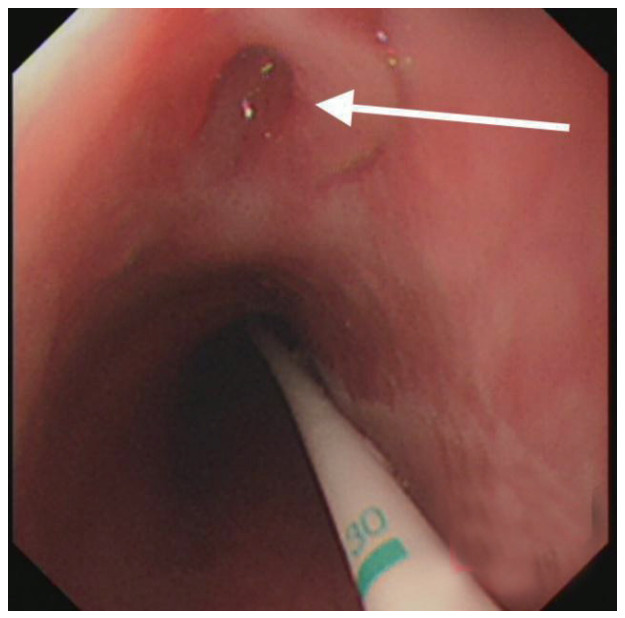

治疗经过:急诊予美罗培南0.5 g,1次/12 h抗感染,补液支持,心包引流等治疗措施,收住感染科后继续抗感染治疗,期间心包积液培养出白假丝酵母菌,加用氟康唑200 mg,1次/d, 口服,心包积液、左侧胸腔积液引流等措施,治疗10 d后复查胸部CT仍有中大量心包积液伴少许积气,纵隔积气;左侧少量胸腔积液,两肺叶间裂少许积液。对照前片(2020.10.26)心包积气及左侧胸前积液有增多,叶间裂积液新发,心包积液略有减少。右肺下叶感染,左肺下叶膨胀不全,较前右肺下叶感染有吸收,左肺下叶膨胀不全新发。考虑不能排除食管纵隔瘘,予口服碘海醇后胸部CT检查(图 3~6):约胸6椎体水平食管纵隔瘘,瘘口为相应水平食管壁右前方可能;胃镜(图 7):食道距门齿25 cm右后壁见一直径约1.0 cm凹陷,内有一小瘘口。胃镜下予钛夹2枚夹闭瘘口(图 8),同时植入空肠营养管。至此患者病情明确诊断食管心包瘘,患者经以上治疗后心包积液、胸腔积液逐渐减少,于11月13日拔除心包及胸腔引流管,因患者签字回当地就诊,予口服莫西沙星、氟康唑带药出院,出院后随访,患者未回当地医院治疗,仅在家中继续空肠营养管饲喂及口服抗菌药物治疗。

| 图 7 箭头所指为食管瘘瘘口,同时可见空肠营养管 |